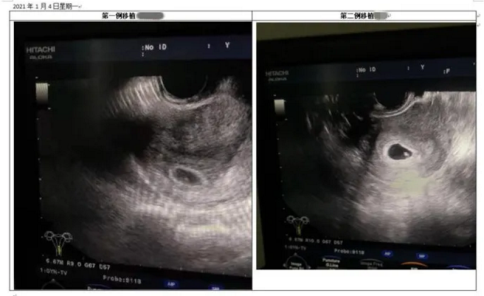

“试管一次顺利了,终究有好孕了!”4日,B超确定宫内妊娠,并顺利看见胎心的侯女士、黄女士兴奋地迎来怀孕喜讯。记者今(6)日从北方医科大学顺德医院(顺德区第一人民医院)得悉,该院的生殖医学核心获取“试管婴儿”技术运作资格后,进行的首批胚胎移植的患者迎来“好孕”。据悉,在去年9月,该院生殖医学核心接受人类辅助生殖技术国度顾问组现场评审,获取常规体外受精—胚胎移植及卵胞浆内单精子显微打针技术(俗称“试管婴儿”)试运作资格,并顺遂通过夫精人工授精(AIH)技术校验。备孕艰巨她们迎来“心肝宝宝”据简介,首例移植顺利的侯女士历经了4年的冗长备孕路,夫妻二人辗转多家医院生殖核心,只为可以早日具有属于自身的宝贝,时期更历经了3次落败的人工授精助孕,备孕之路饱受挫折。另一位患者黄女士和侯女士具有相似历经,备孕3年多时间的她去了许多医院,吃了许多中医、偏方,都没有成效,心里备受煎熬。在得悉该院生殖医学核心获批展开“试管婴儿”技术后,侯女士和黄女士都决议尝试一下“试管宝贝”。经过初期筹备,去年12月7日,两人同时进行“卵泡取出”手术,12月10日进行胚胎移植,12月21日抽血HCG值显著上升提醒怀孕,2021年1月4日B超显现宫内妊娠、看见胎心,两人同时传出喜讯,第一次试管就迎来了“心肝宝宝”。